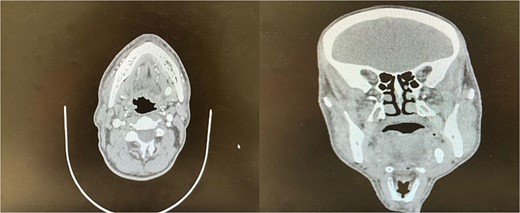

The accuracy of navigation was periodically verified by referencing stable bony landmarks, such as the mental foramen and mandibular condyles, with the navigation probe. Realignment was conducted as needed to ensure consistent anatomical mapping and precise localization of the submandibular stone (Fig. 2). After surface registration, a 1 cm mucosal incision was made intraorally at the nearest point indicated by the navigation pointer, parallel to the anticipated course of the Wharton duct. Blunt dissection was performed to expose the duct, with navigation toward the stone guided by the system. Great care was taken to protect the lingual nerve throughout the procedure. The depth of dissection was gradually advanced by periodically verifying the position with the navigation pointer probe (Fiagon) to maintain precision. During dissection, the stone was accurately located within the gland parenchyma using real-time visualization, and it became palpable, distinguished by its unique color and texture (Fig. 3). The stone was fragmented and removed in pieces because it was fixed (Fig. 4). The surgical field was flushed with saline to remove any residual stone debris, and the incision was closed with 4/0 Vicryl, which is an absorbable suture.

Intraoperative navigation identifying the location of the sialolith.